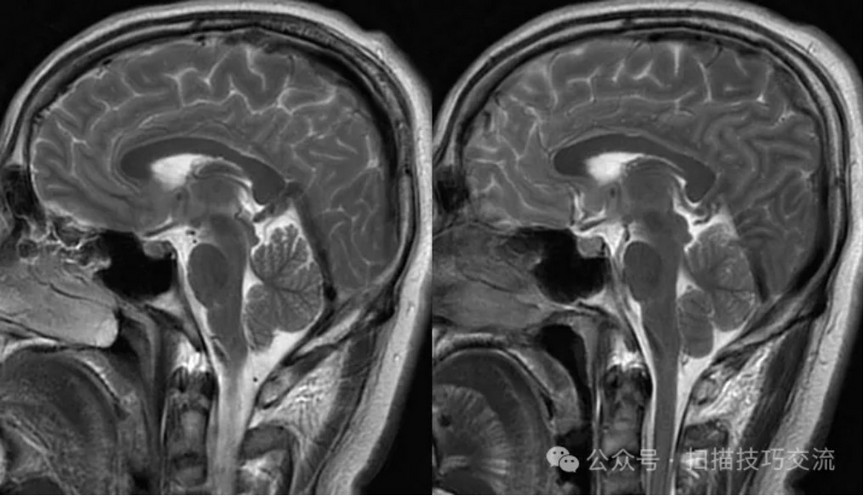

•汗腺分泌:正常,皮肤划痕正常反应。 •尿便障碍:无。性功能障碍无。 •专科情况:正常。不逐一罗列。 •辅助检查:01-05颅脑CT提示:1,上矢状窦、双侧横窦密度较高,请结合临床,必要时进一步检查;2,双侧脑室后角可疑稍高密度影,右顶叶局部脑沟密度可疑增高,建议进一步检查。 •初步诊断:静脉窦血栓

临床申请:颅脑平扫,静脉成像,磁敏感成像,颅内静脉血管黑血成像。

PC-MRV未见异常。

颅内静脉黑血成像,CUBE T1fs w/o +c,静脉窦未见异常。